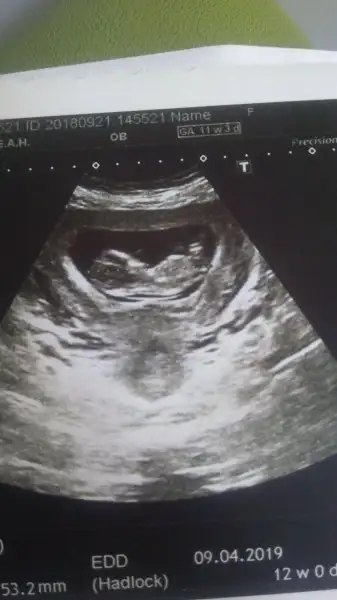

Sagol canim 11+3 ama doktor 12 haftalik dediMaşallah çok güzel görünüyorkaç+kaçtasın canım?

Anladım canım kağıtta yazıyo ben gördüm :) 53 mmAmin canim bir hafta sonra doktorla konusacam boyunu sormadim kizim evde agliyordu diye

Yazıcaktım şimdi bendeAnladım canım kağıtta yazıyo ben gördüm :) 53 mm